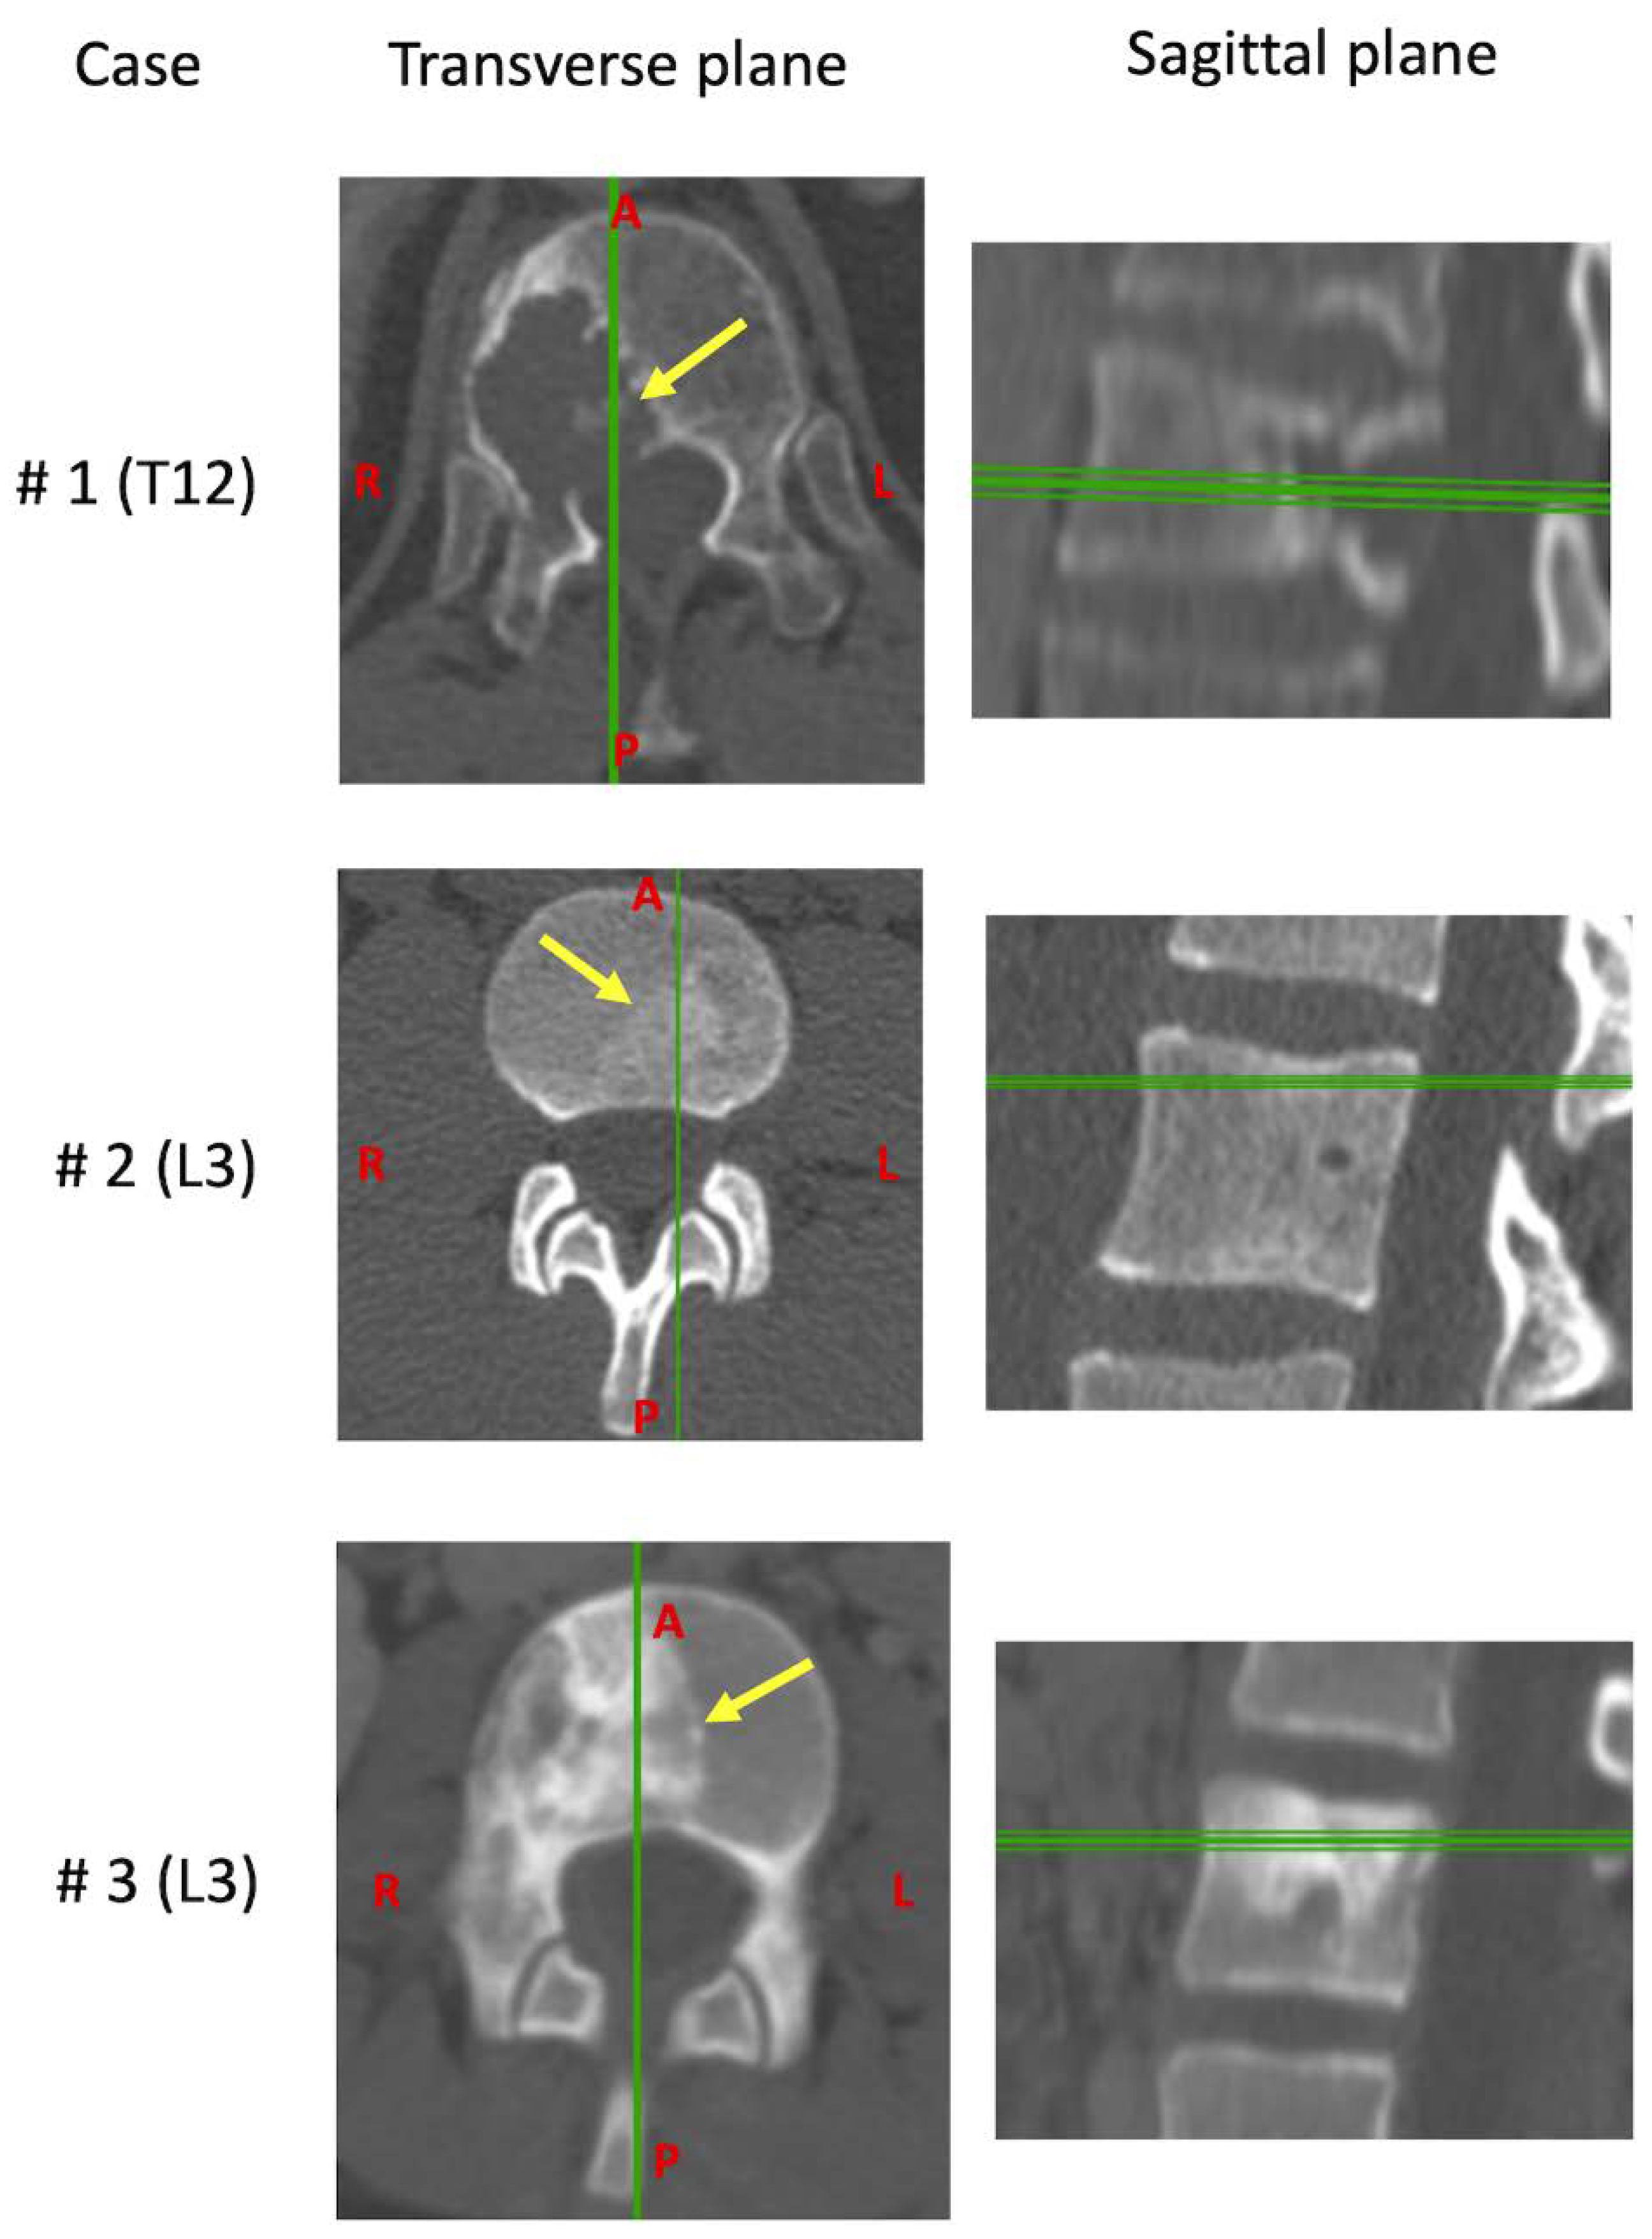

| Case | Age | Sex | Tumors | Vertebra | Grade | Local Extensions | 6-Point ESCC | SINS | Margins Classification | Presence of Metastasis | Months between Diagnosis and Surgery | Previous Therapy | Current Therapy |

|---|---|---|---|---|---|---|---|---|---|---|---|---|---|

| #1 | 62 | M | Chordoma | T12 | IB | 7–10 | 1B | 11 | Focal margin, in the posterior part of the specimen. Wide, the other margins | NO | 2 | None | None |

| #2 | 22 | M | Ewing’s sarcoma | L3 | IIB | 2–6 | 0 | 4 | Wide (Necrosis 40%, Bologna system 1) | NO | 4 | Chemotherapy | Chemotherapy and Radiotherapy |

| #3 | 11 | F | Ewing’s sarcoma | L3 | IIB | 7–11 | 1A | 6 | Wide (Necrosis 80%, Bologna system 1) | NO | 6 | Chemotherapy | Chemotherapy and Radiotherapy |